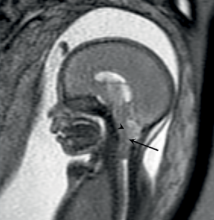

In an analysis that included more than 1.4 million births, exposure to magnetic resonance imaging (MRI) during the first trimester of pregnancy compared with nonexposure was not associated with increased risk of harm to the fetus or in early childhood.